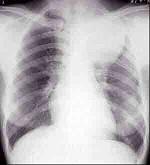

问题 女,25岁,胸背痛2周,胸片如图,最可能的诊断为()

选项 A.左上肺不张 B.左上肺炎 C.纵隔肿瘤 D.左上肺癌 E.左上肺炎性假瘤

答案 C